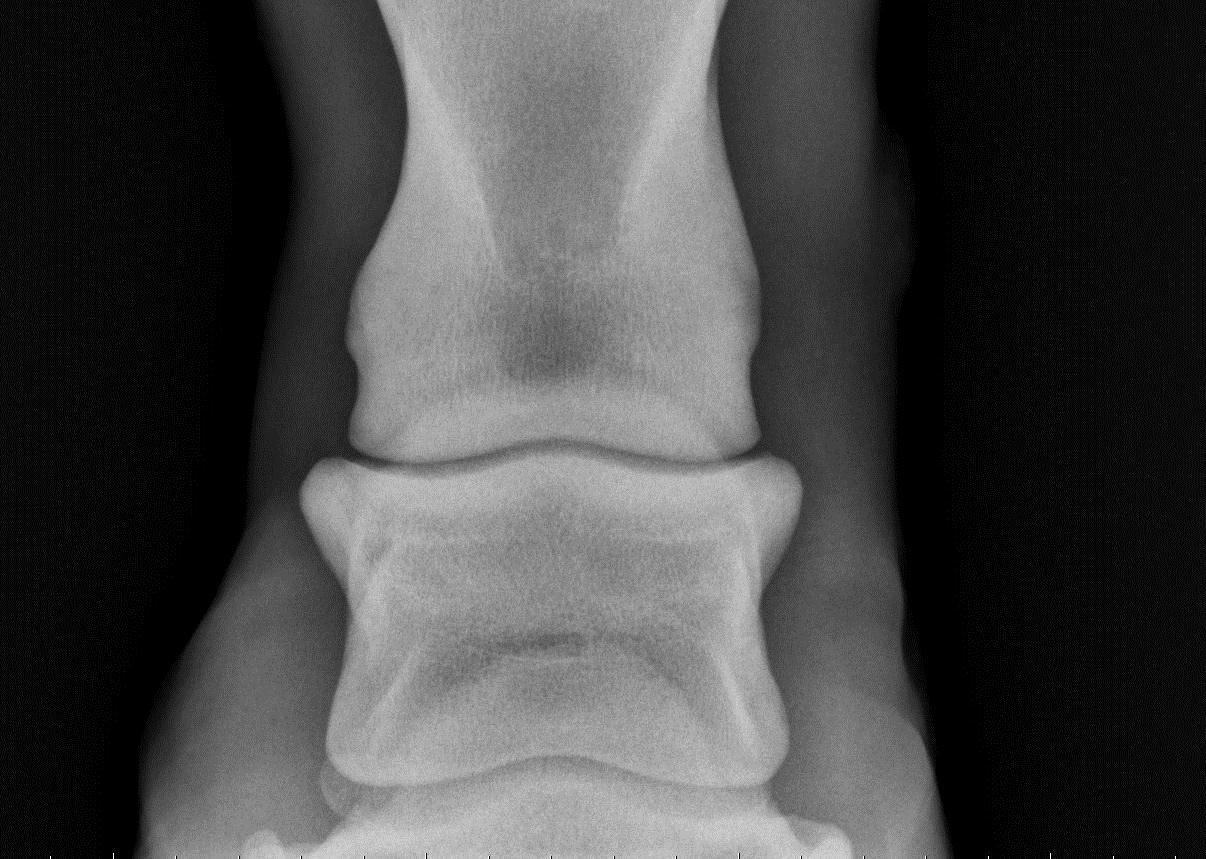

Osteoarthritis is a chronic, progressive disease where the cartilage, soft tissues, and bones deteriorate in articular joints, which causes pain when your horse moves. Ringbone is a term for osteoarthritis that specifically occurs in the pastern and (or) coffin joints in a horse's lower limbs.. Ringbone is a disease that does not discriminate; horses of all breeds, ages, and functions can be at risk. An arthritic, degenerative disease of the pastern and coffin joints, ringbone comes in two types. High ringbone affects the pastern, and low ringbone affects the coffin. Similar to arthritis in people, ringbone develops in our equine.

Physical signs of ringbone include swelling or a hard lump around the pastern or coffin joint. This might be more evident when the horse is standing on a hard surface or after a workout. In such instances, using a cooling wrap like the Ice Horse Tendon Wraps can help alleviate swelling and offer relief to your horse.. Then, inflammatory cells release toxins which create tissue damage and thin joint fluid. As damage increases, the body responds by producing scar tissue, which can then progresses into bony development. Ringbone in horses can produce the following symptoms: pain, swelling, lameness, heat, and tenderness.